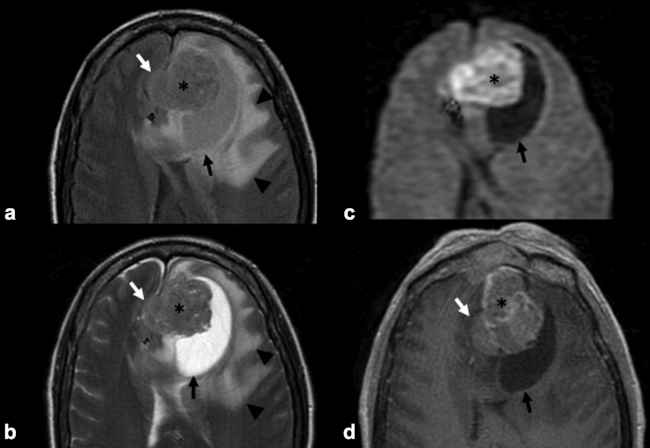

La RM es la prueba de imagen de elección para evaluar los detalles de la extensión y la estadificación locorregional del tumor. La RM es superior a la TC para determinar el grado de afectación del tejido blando (►Fig. 9) con una mejor evaluación de la afectación intracraneal (►Figs.10,11,12,13,14), orbital (►Figs.14y15), de la base del cráneo y la invasión perineural.53,54 La RM tiene un valor añadido para distinguir la afectación dural de la del parénquima cerebral (►Fig. 12).55 En la RM, el NBO aparece hipointenso respecto a la sustancia gris en imágenes ponderadas en T1 y de isointenso a hiperintenso en las imágenes ponderadas en T2 (►Figs.10,11,12,13,14,15).56 Muestra un realce homogéneo, excepto en áreas con hemorragia o necrosis. Además, permite diferenciar las secreciones retenidas del tumor, al ser estas hiperintensas ponderadas en T2.53,55 Los hallazgos de imágenes clásicos incluyen una masa “en forma de mancuerna” que se extiende a través de la placa cribiforme (►Fig. 12), con la parte estrecha a nivel de la placa. Los quistes tumorales periféricos (►Figs.5b,12,14,16) y las calcificaciones moteadas son bastante característicos de NBO.1

La evaluación del tumor recurrente debe incluir tanto TC como RM. Las características de imagen del tumor recurrente no difieren de su apariencia en la presentación inicial. Se ha sugerido el siguiente protocolo de seguimiento para detectar precozmente las recurrencias: RM con contraste 2-4 meses después de completar todo el tratamiento. Posteriormente, se repite cada 4-6 meses durante 5 años, y pasado ese tiempo, se realiza anualmente durante la vida del paciente.59 El protocolo de RM utilizado en nuestro servicio consiste en la realización de secuencias ponderadas en T1, T2 y T1 con supresión grasa sin y con contraste para el estudio a nivel nasosinusal y secuencias ponderadas en T1, T2, FLAIR, DW-EPI y T1 con contraste para el estudio encefálico. Además, se debe hacer una radiografía de tórax anual para excluir la presencia de metástasis.59